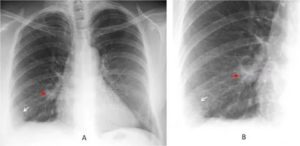

На рентгене прослеживается характерное треугольное затемнение с основанием к периферии легкого в средних и базальных сегментах. Однако, выраженный венозный застой и отек паренхимы могут сглаживать рентгенологические проявления.

Важно! При реализации рентгенографии на снимке видны затемненные области на пораженном легком.

Инфаркт легкого диагностируется с помощью рентгена, так как только с его помощью обнаруживается высокое положение купола диафрагмы, то, насколько расширены корни одного из легких, плевральный выпот, и некоторые другие отклонения.